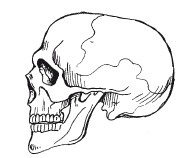

Ahhoz, hogy a tetején a gerinc csatolt koponya. Ő 29 lapos csontokban. Kerek rész (nevezetesen azt, mint tudja, az agy) áll 8 csontok, az arc, valamint az alsó állkapocs - 14 csontok, vannak csontok a fül - három-három, és egy csont a torkán (hyoid).

Skull (rögzített közös)